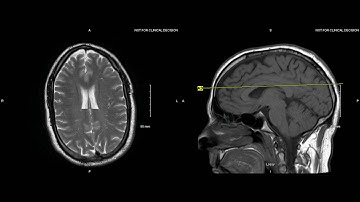

Unremarkable Non-Contrast CT Axial Bone Window-Example 3